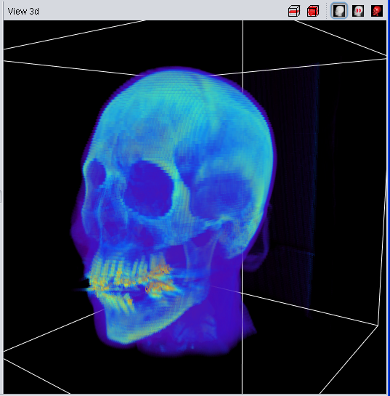

An enhanced 3D visualzation feature is the 2D-Texture Visualization. It basically renders several slices in transversal, sagittal and frontal projection with a low transparency value, allowing a fast and 3 dimensional analysis of the loaded data set. It can be enabled using the "3d View" main menu or the button in the "View 3d" title bar.

The quality of the 2D-Texture Visualization strongly depends on the number of planes which are rendered. This can be choosen in the "View 3d" tab of the main tool pane. Select "1" for the best results - and the highest main memory consumtion. The overall transparency allows to look "through" the data to analyse internal structures and it is possible to choose between a "grey scale" and "pseudo color" colortable.

| Volume Data using 2D Texture | Volume Data using 3D Texture |

The 3D-Texture Visualization is very similiar to the 2D-Texture Visualization, but usually with a usually improved rendering quality. Since not all graphic cards support 3D-textures (yet), both visualization features have been implemented. If the "View 3d" shows only a "white box" instead of the loaded data, your graphic card does not support 3D-Textures.